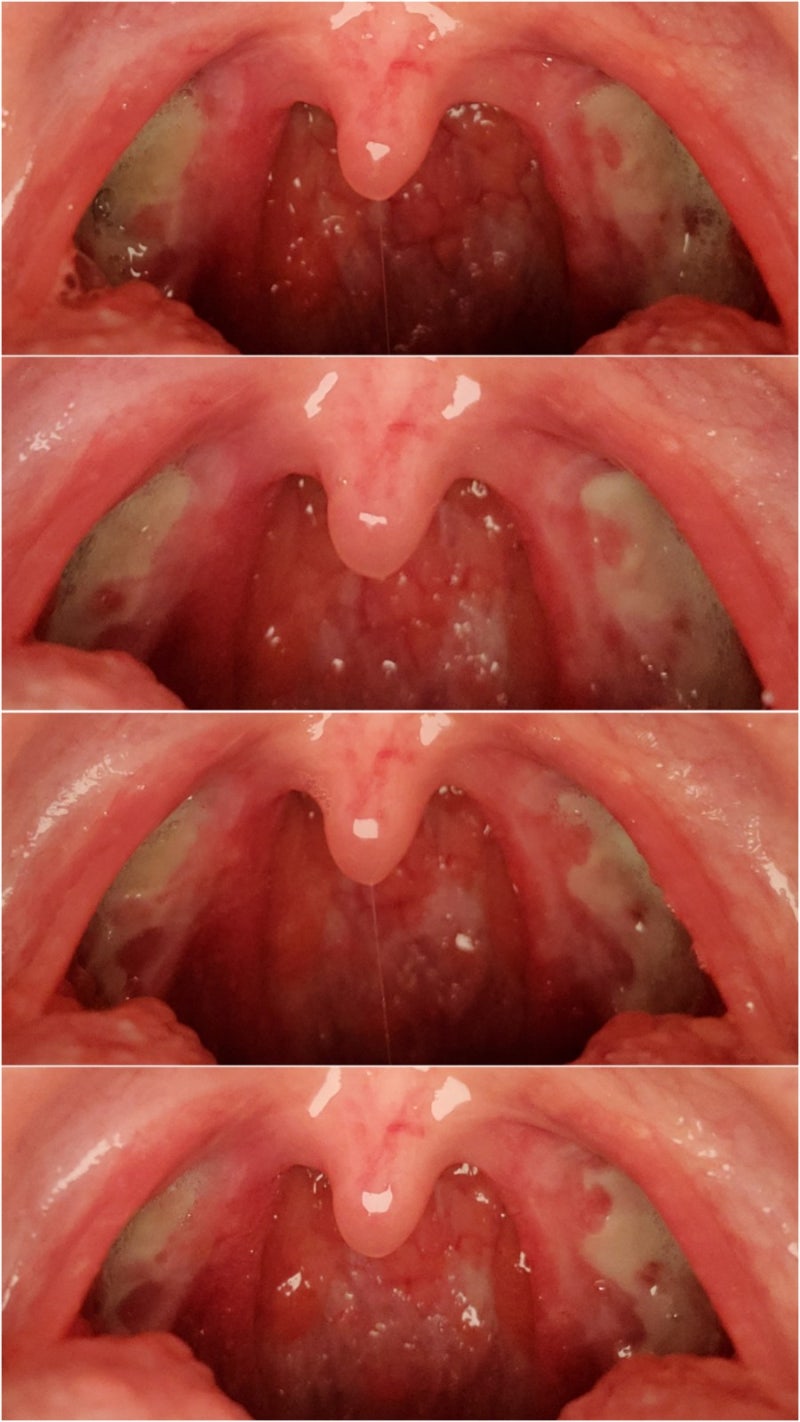

편도선 절제술을 받기로 결정한 대부분의 사람들은 크게 두 가지 이유 때문에 그렇게 한다고 생각합니다. 1. 만성 편도염 2. 편도선이 불편하다고 말씀하시면 의사가 편도선을 검사하여 수술이 가능하다고 알려줄 것입니다. 만성 편도선염 환자의 수술 기준은 “연 3회 이상 또는 심한 편도선염”이라고 생각합니다. 남편이 몸이 너무 아파서(결혼식 당일에도) 다른 병원에서 이송하라는 권고를 받았습니다. 출처: 서울아산병원 편도결석은 편도선에 음식물 찌꺼기와 박테리아가 모여 형성되는 쌀알 크기의 작고 노란 입자 또는 편도선의 작은 구멍입니다. 그래서 편도결석 압박이 있는 분들이 편도선염이 있는 분들보다 편도선 제거에 더 만족하실 것 같아요. 많은 여성들이 편도결석 때문에 수술을 결정하는 경우가 많으니 혼자 고민하지 마시고 상담을 받아보세요. 정기적으로 이비인후과에 가면 뺄 수 있지만 일단 없어지면 재발하기 쉽다고 한다. 편도선은 만 5세(?) 이후에는 거의 쓸모가 없는 장기라고 합니다. 편도선 제거와 면역력 저하 사이에는 관계가 없다고 합니다. 수술 전 검진은 병원마다 다르지만 보통 심전도, 미각검사, 혈액검사, 소변검사, 음성녹음(전후), 흉부엑스레이 등입니다. 메세지를 전달해주세요! 남편에게 갑상선 문제가 있습니까? 예전에 받았는데 수술 전날 까먹고 생각나서 급히 다시 갑상선 검사를 했어요. 약물 사용 이력이 있는 경우 마취 전문의에게 알려야 합니다(비밀 사항이므로). 전신마취는 정말 위험하다고 합니다. 검사 비용은 종합병원에 가는 것과 비슷합니다. 남편은 나보다 2000원 적게 냈다. 어떤 부분을 추가로 체크하느냐에 따라 금액이 달라지는 것 같습니다. 저는 약물 알레르기가 있어서 아마 추가된 것 같습니다. 갑상선, 혈압 등 다른 질환이 있으신 분들은 정밀검사를 하셔야 하는 것으로 알고 있습니다:) 검사부터 수술 전 기간까지 마음껏 드셔도 됩니다! ‘일주일만 기다려’가 될 수 없습니다! 수술 전 주부터 매운 음식(2주 동안 먹지 못함)을 조심하고, 영양제(예: 오메가 3 – 출혈 문제) 섭취를 중단하고 가능하면 허브나 주스를 피하십시오. 수술 전 입원부터 퇴원까지의 편도선 절제술은 DRG 종합부담금 제도와 연계되어 있어 장기간(일반적으로 2박 3일에서 3박 4일) 입원이 불가능하다. 병원에서도 못 읽으면 다시 읽어보라고 하더군요. <종합지불제> 이 제도는 진찰, 검진, 수술, 주사, 약 등 치료의 종류나 금액에 관계없이 환자가 일정액의 진료비를 부담하는 제도를 말합니다. 진료의 종류나 금액과 관계없이 환자에게 제공되는 의료서비스의 종류나 금액에 따라 소정의 진료비를 미리 의료기관에 지급) 산정에 있어 병·의원과의 분쟁은 없다. 하지만 의료서비스의 질이 떨어지는 것이 한계로 지적됐다. 네이버 병원마다 수술 방법이 다를 수 있지만 저희는 코블라테이터 수술 방법을 선택했고 지금 치료를 받고 있지만 후회는 없습니다. 내가 가진 수술로 3kg을 더 뺄 수 있을지 궁금했다. 무과금 상품이지만 실비보험에 가입되어 있으니 본인에게 너무 큰 부담을 더하실 필요는 없습니다. 실제 보험 적용 범위의 90%를 받는 사람도 있고 80%를 받는 사람도 있습니다. 보험 약관을 참조하십시오. 수술 전 주의사항 10시간 빠른 항생제 반응 테스트 팬티 벗기 귀금속 제거를 위한 펌프 물 댓글에서 보시다시피 저에게 가장 힘들었던 것은 주사하면서 수술용 수액을 넣는 것이었습니다. 혈관이 짧고(?) 약해서 바늘이 다 뚫려 있고, 바늘이 굵고 통증이 있어 금식보다 더 불편합니다. 멍은 사진보다 5배정도 심해서 2주 정도 멍이 들고 못생겼습니다. 입원하는 동안 손이 붓고 아프고 많이 힘들었습니다. 항생제 반응 검사도 전날 진행하였고, 수술 전 이른 아침까지 금식 후 예정대로 순차적으로 수술을 진행하였습니다. 아이들이 끝나고 들어가서 9시쯤 수술을 받을 수 있었습니다. 내 시간이 맞는지(수술이 많은 시간이 아님) 기다리는 환자가 많지 않기 때문에 아침 일찍 들어갈 수 있다. 가능한 한 빨리 수술을 받는 것이 좋습니다. 수술실에 들어가면 마취과 선생님이 몇 가지 질문을 하시는데 대략적으로 대답을 하시면 나른한 상태에서 등을 두드려 맞으셨다고 확신하실 수 있습니다(수술완료). 그랬는데 간호사가 10분 정도 등을 토닥거려 주셨어요. 나는 기침을 조금 하고 있었지만 최대한 조심스럽게 뱉어냈다. 그리고 어쩌다 보니 수술 4~5일째까지 하루에 2갑씩 20년을 피웠는데 목소리가 나와서 좀 힘들었다. 나중에 자연스럽게 돌아오므로 너무 걱정하지 마세요. 이렇게 수술 후 무통주사를 맞았는데 저조차도 무통주사가 마음에 들지 않아 처음에 빼버렸습니다. 남편은 괜찮았고 통증이나 기침, 메스꺼움도 없었습니다. 대부분의 주사는 저에게 어렵습니다. 종종 여성들은 주스나 주사에 민감하다고 말할 것입니다. 수술 당일(1일차)부터 입원 3일차까지의 일방통행 사진입니다. 골고루 잘 먹으면 출혈의 가능성이 줄어든다고 하니, 아프더라도 조금씩 조금씩 규칙적으로 드시기를 바라겠습니다. 아침저녁이 제일 힘들다(남편도 마찬가지). 다시는 아침의 고통을 겪고 싶지 않다. 통증이 너무 심해서 눈을 뜰 수가 없었습니다. 수술 후에는 금식을 깨고 아이스크림을 자주 먹는 것이 가장 좋습니다. 딸기, 초콜렛 X (피가 나면 보기 힘들거나 헷갈릴 수 있음) 요거트 아이스크림은 케밥처럼 생겼는데 저는 괜찮았습니다. (조금 아프다) 바닐라아이스크림 싫어해서 이것만 먹자. 남편은 투게더에서 엑설런트를 많이 먹는다. 병원에서는 아침, 점심, 저녁에 죽만 제공됩니다. 저희는 맛있어서 조금 먹었는데 어떤 곳은 미음만 나옵니다. 1인당 총 금액입니다. 여기에는 수술비+(2인실)입원비+치료비가 모두 포함되어 있습니다. 다른 부수적 비용은 지불하지 않았습니다. 저희는 종합병원 수준이라 더 저렴한 것 같습니다. 대학병원 수준으로 가시면 비용이 조금 더(약 100만원) 나옵니다. 각 회사는 어떨지 모르겠지만 남편 회사는 이 부분을 잘 해줘서 정말 운이 좋은 것 같아요. 일을 하고 있다면 확인하고 휴식을 취하세요. (개인적으로 최소 5일 이상 권장) *말하는 것 자체가 상처가 되니 직업이 주로 가르치는 일이나 말하는 일이라면 일주일 정도는 무리하지 마시길 바랍니다. 그리고 많은 사람들이 맛이 변하는 것에 대해 걱정합니다. 남편의 취향은 변함이 없습니다. 반대로 짠 음식은 더 맛있습니다. 맛이 변한 이유는 수술 중 혀를 눌렀고 그 부위의 신경도 함께 눌렀기 때문이다. 격한 운동이나 격렬한 활동을 하지 말 것 10 lbs 이상 들어올리지 말 것(US Doctor Special) 마약성 진통제를 처방받은 경우 주의(US Doctor Only) 금단 음식: 짜거나 매운 음식(각성제), 탄산음료, 오렌지 주스, 뜨거운 음료 음식, 딱딱하고 거친 음식, 빨대 금지, 재채기, 기침 및 가래 금지. 얼음으로 가글하고 양치질을 자주 하여 입안을 청결하게 유지하십시오. 한 달 동안 술과 담배를 하지 마십시오. 사우나, 공중 목욕탕 또는 사우나에 가지 마십시오. 몸이 아파서 먹지 않으면 4~7일에 과육이 떨어질 때 출혈의 위험이 있다. 평소보다 훨씬 잘 먹는다. 적은 양의 식사를 더 자주 먹어야 합니다. 통증은 6일과 7일에 가장 심했습니다. 이때 귀가 너무 아파서 정말 아무것도 하기 싫었다. 약을 먹어도 통증이 가라앉지 않아 밤에 펜잘을 하나 더 먹었다. (보통 게보린은 피가 나니까 먹지 말라고 하고, 약을 더 먹고 싶으면 의사와 상담하세요.) 보통 타이레놀을 더 먹으라고 하는데 저는 타이레놀을 많이 안 먹거든요. a penza about 8th 첫날 고블이 떨어져 피가 조금 나고 이때가 가장 고통스러웠다고 합니다. 많은 분들이 편도선 절제 후 ‘하늘을 삼키는 느낌’ 이라고 하시는데 저는.. 어느 정도 일까요? 아프면 삼키면 뱉어내고 싶을 정도로 아파요. 8~11일 7~10일 제품이 떨어지기 때문에 출혈의 위험이 높습니다. 물론 일주일이 지나면 몸의 잔털이 빗질된 느낌이 듭니다. 통증은 7일과 8일에 최고조에 달했고 약간 가라앉은 것 같았습니다. 귀의 통증은 여전히 존재합니다. 병원에 있을 때는 귀가 아프지 않았는데 퇴원하고 나서 정말 아팠던 것 같다. 아침에 일어나면 귀를 막고 있을 정도로요. 의사는 귀 통증도 인후염이라고 말했습니다. 저는 개인적으로 어렸을 때부터 귀가 좀 약해서(수술 경험이 있어서) 더 예민해진 것 같아요. 사실 8일째부터 남편과 저는 맵고, 맵고, 맵고, 빼고 다 먹었던 기억이 납니다. 가장 많이 먹어도 피가 안 터지는 걸 보면 너무 많이 먹은 것 같은 느낌이 들 수도.. ㅋㅋ 일반식의 경우 밀국수나 냉면을 잘게 다지는 것을 추천한다. Days 12-14 Days 12일 이후에는 확실히 탈락자가 많았습니다. 고통을 덜 느끼고 싶습니다. 그것은 결코 완전히 사라지지 않았습니다. 키위를 함부로 먹고 수술 직후 통증을 맛보았다. 부주의는 절대 금지입니다. 외래진료(12일차)에서 의사선생님이 1주일이 지나면 매운 음식을 먹을 수 있다고 하더군요. 통증이 완전히 사라지려면 약 3주 정도를 고려하는 것이 좋습니다~ 15-18일 이상) 힘든 상태에서 15일까지 약물을 복용하지 않고 18일 이후에 약물을 중단합니다. 1일: ●●● ●○3일: ●●●●● 1일 4: ●●●● 5일: ●●●● 6일: ●●●●●○ 7일: ●●●●● 8일: ●●●●○ 9일: ●●● 10일: ●●● ○ 11일차: ●●●● 12일차: ●●●○ 13일차: ●● 14일차: ●○ 사람마다 통증 역치가 다르다고 합니다. 1) 통증을 자주 느끼시는 분, 2) 처음에는 괜찮으나 이후 통증으로 떨리는 분, 3) 통증이 점차 감소하는 분. .. 물론 1등하고 10일까지는 힘들었는데..그러더니 통증이 가라앉고 지금은 13일부터 2주정도 맵거나 너무 뜨거운 음식 빼고는 아주 심하게 먹습니다. 2주의 기적을 믿으세요… ! 제 편도선 절제술 후기입니다 궁금하신점은 남겨주세요~ 제 편도선도 제가 직접 공개했습니다 공감 팔로우 잊지 않으셨나요?